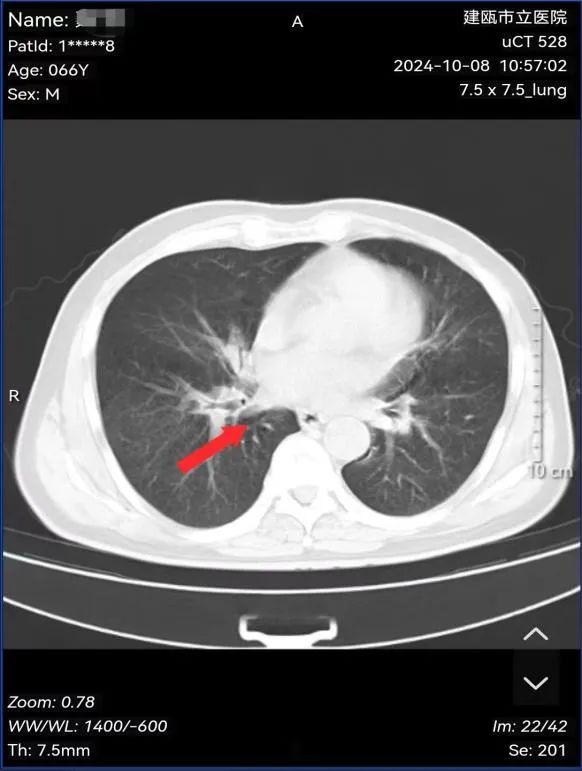

魏先生,男性,66岁,有长期吸烟史20余年,因反复咳嗽数月求诊我院,经肺部CT、支气管镜等检查确诊小细胞肺癌。经肺癌多学科诊疗小组专家会诊:建议完善骨ECT、脑部MRI检查后明确分期为:局限期小细胞肺癌,建议行同步放化疗治疗。

图为:治疗前病灶影像及病理结果